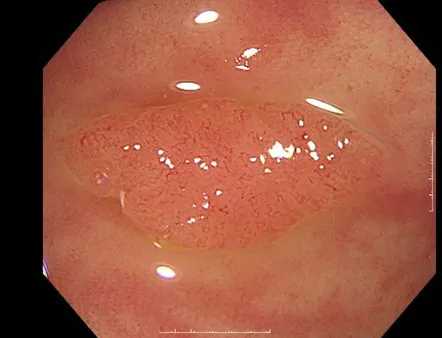

大腸カメラの症例

高倍率光学ズーム搭載の拡大内視鏡

当院で採用している4K対応、高解像度の内視鏡用モニター、オリンパス®「OEV321UH」+大腸ビデオスコープ「CF-XZ1200I」により、最大拡大倍率135倍の高倍率・高画質拡大観察が実現可能です。また、高感度CMOSイメージセンサーの採用により、ノイズが少なくハイビジョンを上回る高画質(HQ画質)で観察することができます。